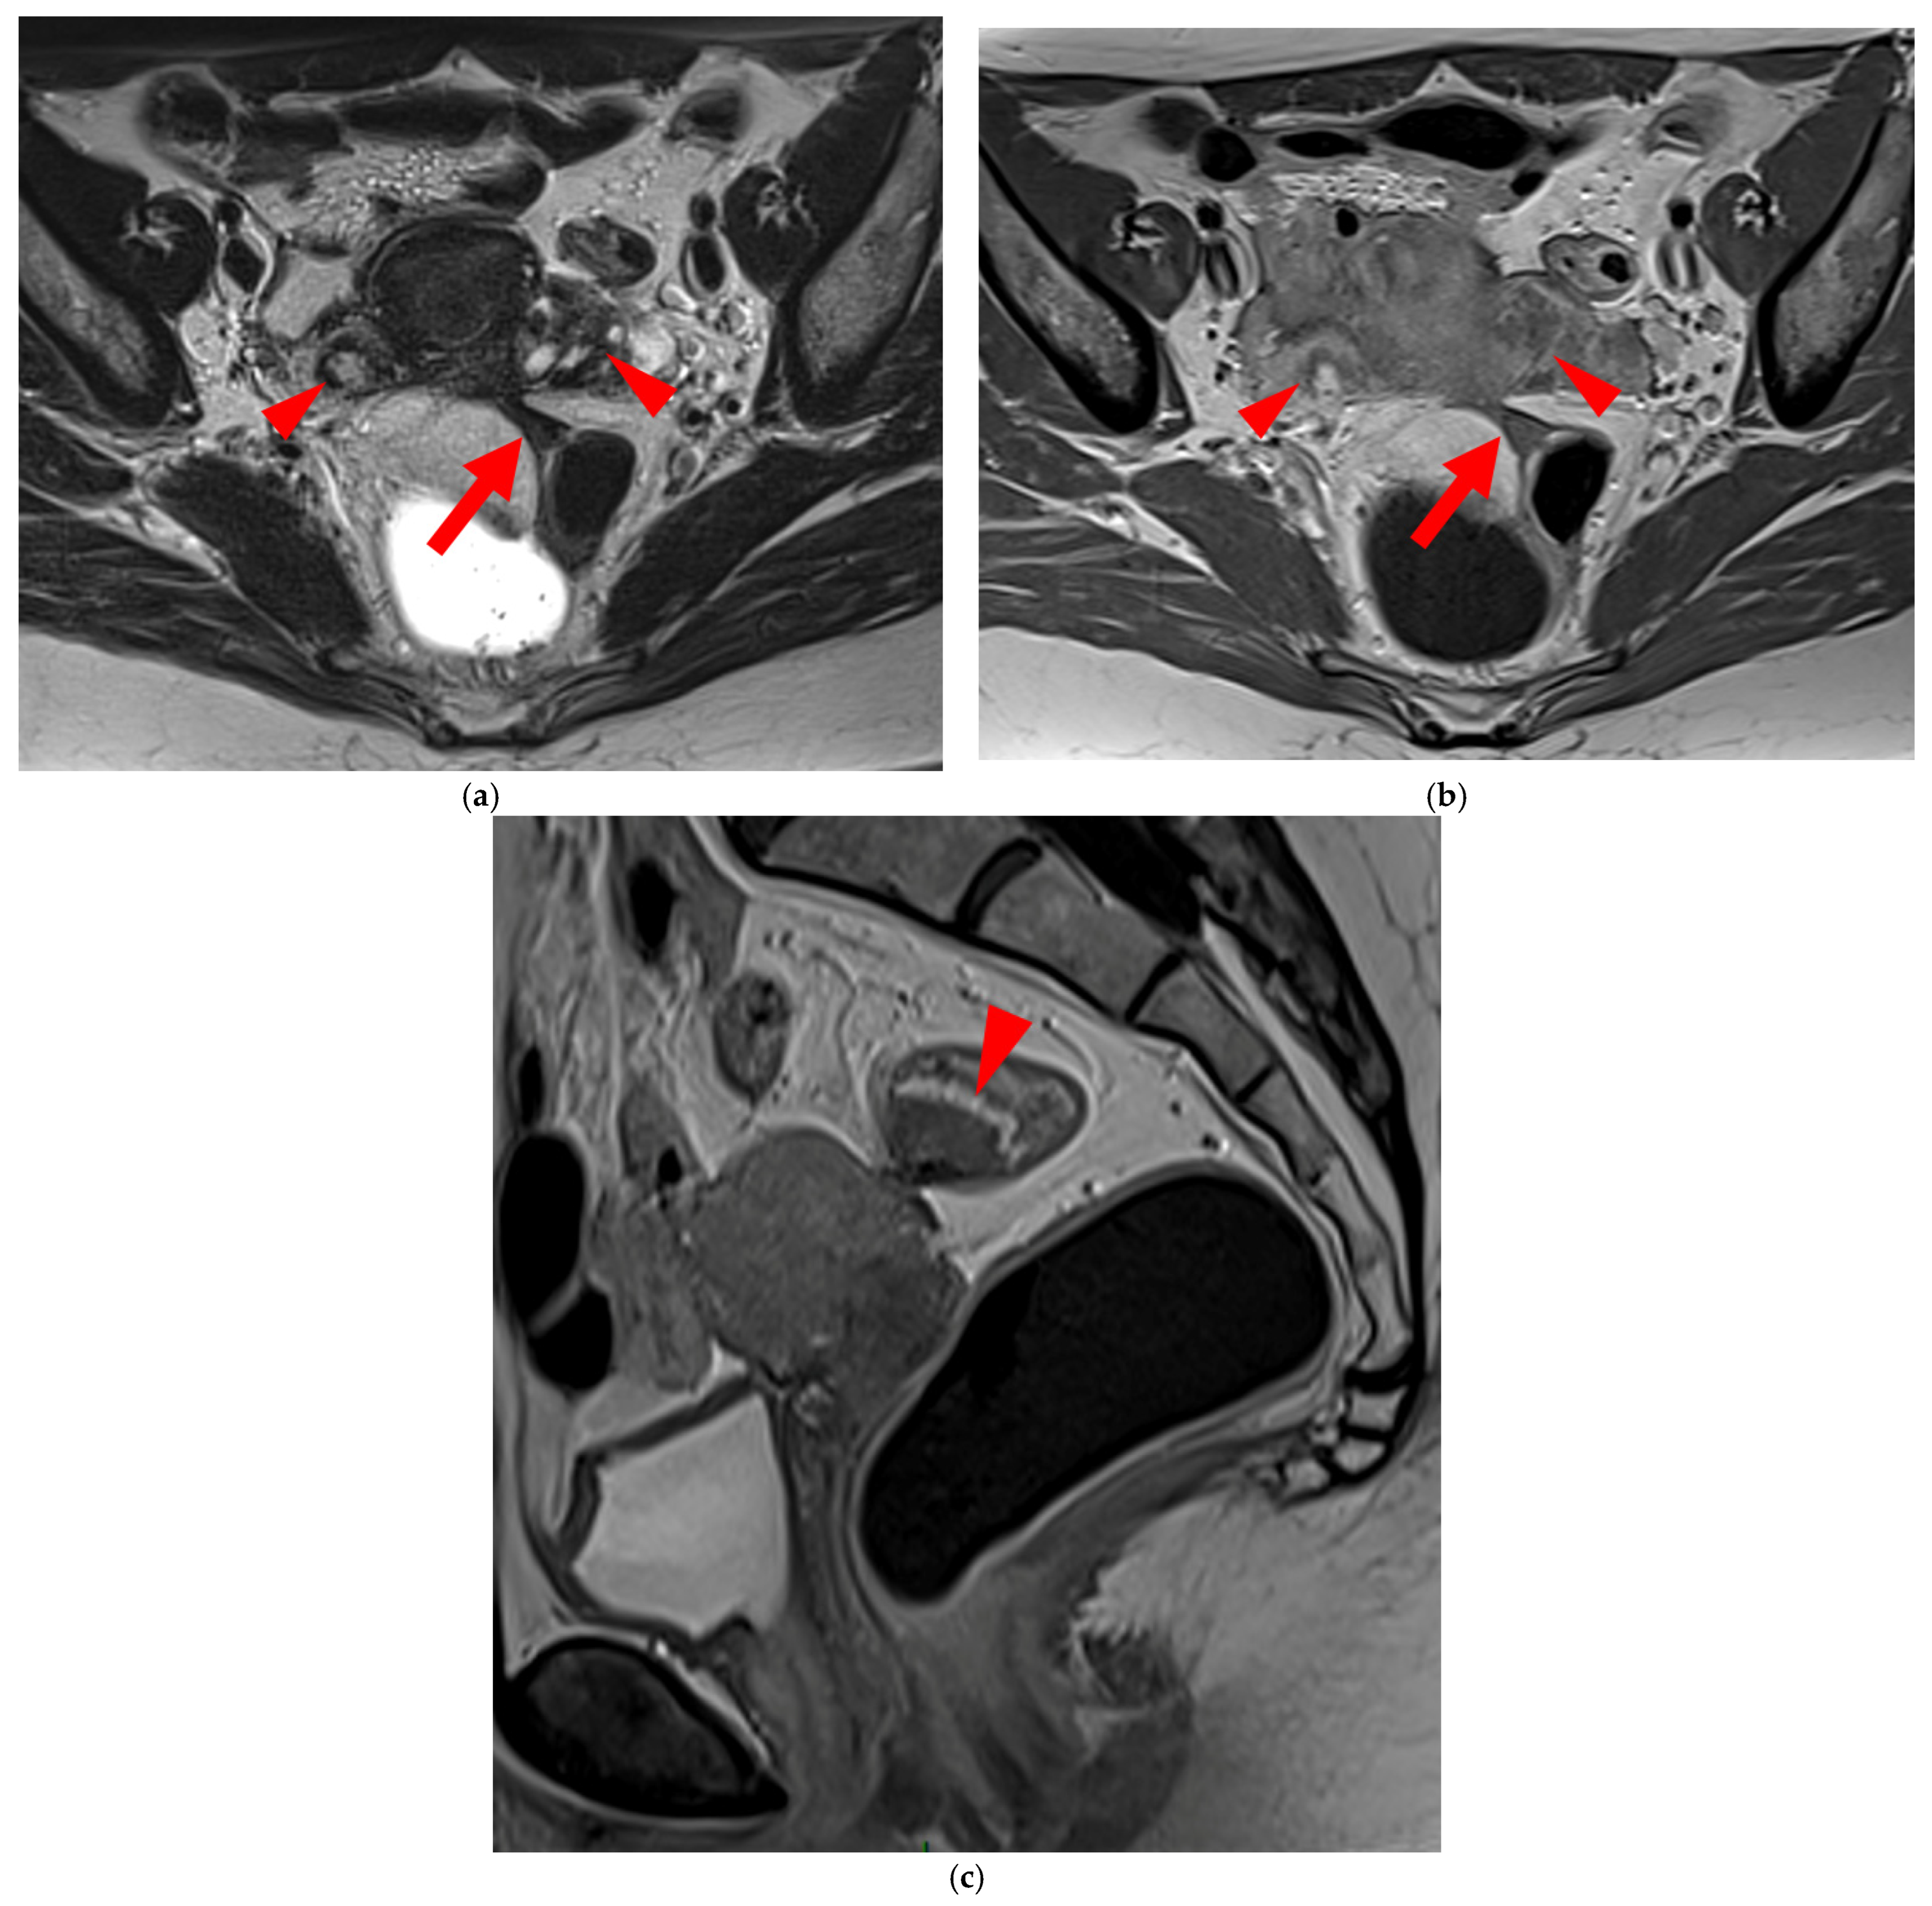

A type 5 USL appears nodular and can be classified either as type 5A or type 5B.

A type 5A USL (Figure 6) is nodular with a smooth contour.

A type 5B USL (Figure 7) is nodular with spiculated margins. A type 5B USL may also display an isolated nodule with microcystic content.

Figure 6. Pelvic MRI scans of two patients with HTD type 5A USLs. (a,b) Sagittal T2WI: nodularity with regular margins (arrows) within the right USL (arrowheads).

Figure 7. Pelvic MRI scans of two patients with HTD type 5B USLs. (a) Patient 1: sagittal T2WI shows a microcystic nodule (arrow) within the origin of the right USL (arrowhead). (b,c) Patient 2: axial (b) and sagittal (c) T2WI show a nodular left USL with spiculated margins (arrow) and a right ovarian endometrioma (arrowhead).